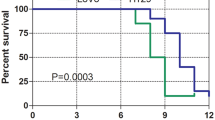

The most important issue in the establishment of a liver metastasis xenograft model is to determine the optimal time for PET imaging. The survival time of the liver metastasis mouse model is generally shorter than that of the traditional subcutaneous tumor model. Considering the time of imaging of multiple tracers, we determined the optimal imaging time as 8 weeks after tumor cell inoculation. Figure 1 shows LoVo and HCT8 models 18F-FDG, 18F-FLT, and 18F-FMISO PET images and their corresponding liver anatomy. The LoVo model rat liver metastasis rate is 50% (9/18), HCT8 model rat liver The metastatic rate was 35% (7/20). The difference between the three tracer SUVmax values between LoVo and HCT8 liver metastases was analyzed using an independent sample t-test. The results showed that there was no significant difference between the 18F-FDG SUVmax value and the SUVmax ratio of LoVo and HCT8 liver metastasis (P = 0.057 and 0.286) (Table 4, Fig. 2). However, there was a significant difference between the 18F-FMISO and 18F-FLT SUVmax and SUVmax ratio values of LoVo and HCT8 liver metastasis tissues, which was statistically significant (P < 0.05). And the 18F-FDG SUVmax values of the two cells were significantly higher than the SUVmax values of 18F-FLT and 18F-FMISO, which was consistent with the results of in vitro cell uptake experiments. It can be seen that 18F-FDG is more sensitive to liver metastases, but its specificity is poor.

The protein expression levels of MACC1 (0.457 ± 0.017 and 0.206 ± 0.016) and SPON2 (0.419 ± 0.015 and 0.267 ± 0.026) in LoVo liver metastasis were higher than those in HCT8 (P < 0.0001, P = 0.0003). Our results indicate that in vivo experiments, the expression of MACC1 and SPON2 in high metastatic potential LoVo cells is higher than that of low metastatic potential HCT8 cells (Fig. 4).

Linear regression analysis

Figure 5 shows the correlation between MACC1 and SPON2 protein expression and PET SUVmax ratio in different cell liver metastases; Fig. 6 shows the correlation between MACC1 and SPON2 protein expression. Linear regression analysis showed a significant positive correlation between MACC1 and SPON2 (r = 0.763, P = 0.0015). Correlation analysis of 18F-FLT SUVmax ratio showed that the 18F-FLT SUVmax ratio was significantly positively correlated with the expression of MACC1 and SPON2 in hepatic metastasis (r = 0.737, P = 0.0026; r = 0.842, P = 0.0002). Correlation analysis of 18F-FMISO SUVmax ratio showed that the 18F-FMISO SUVmax ratio was significantly positively correlated with the expression of MACC1 in hepatic metastasis (r = 0.770, P = 0.0013).

Correlation analysis between MACC1 and SPON2 and three tracers in LoVo and HCT8 liver metastases (n = 14). a There was a significant positive correlation between MACC1 expression and expression of 18F-FLT SUVmax ratio and 18F-FMISO SUVmax ratio in liver metastasis. b There was a significant positive correlation between the expression of SPON2 in liver metastases and the expression of 18F-FLT SUVmax ratio